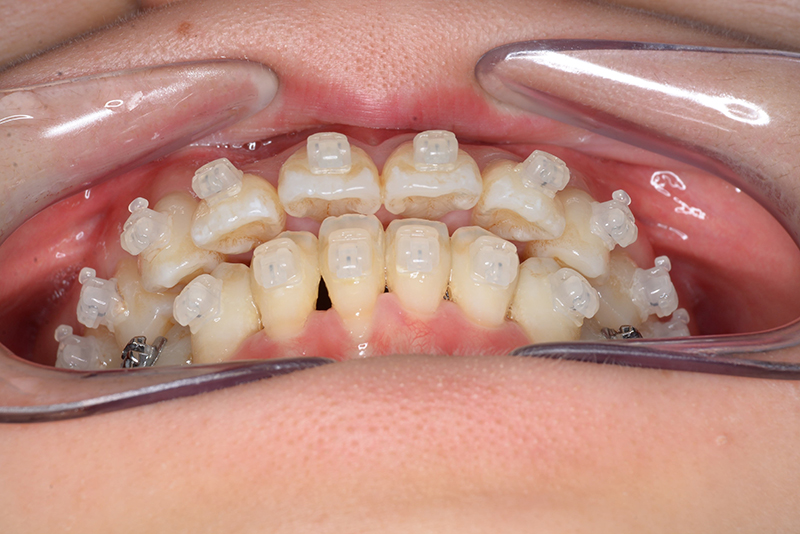

FP・IOP

主訴 口が閉じづらい 診断名 アングルⅠ級上下顎前突症例

口腔内所見 over jet 4.0mm、over bite 2.0mm、臼歯関係Ⅰ級、犬歯関係Ⅱ級で上顎前歯は唇側傾斜を呈しており、上下顎前突の様相を呈していた。